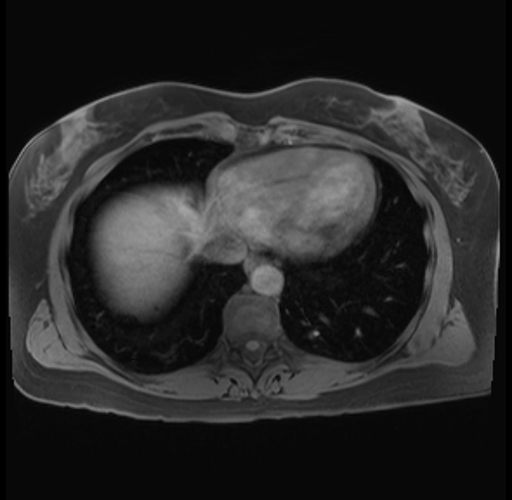

Imaging Analysis

Look through the patient's CT scan to identify any areas of concern for the necessary procedure.

Based on your CT findings, which issue(s) are present and would give reason for "planned slowing down moment(s)" in this case?